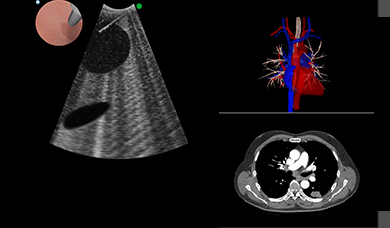

With the BRONCH Mentor simulator you can enjoy a flexible, all-inclusive, and highly reactive training environment.

It provides a comprehensive solution for flexible bronchoscopy training of pulmonary and critical care physicians, thoracic surgeons, anesthesiologists, interventional pulmonologists and others. Fundamental skill tasks and complete clinical procedures provide an optimal learning environment for motor, cognitive and coordinative skills acquisition, as well as diagnostic and therapeutic clinical hands-on experience towards competency.

- Realistic and comprehensive bronchoscopic simulation training away from patient, designed to support both team and solo training sessions

The endobronchial ultrasound assessment tool could be used to provide reliable and valid assessment of competence in EBUS-TBNA, and act as an aid in certification. Virtual-reality simulator training was shown to be more effective than traditional apprenticeship training.

The simulator demonstrated validity in differentiating skill in scope manipulation and airway anatomy, but did not discriminate skill levels in anatomic orientation or identification of lymph nodes. Bronchoscopy simulation was viewed as helpful by all levels and should be considered before performance on patients.